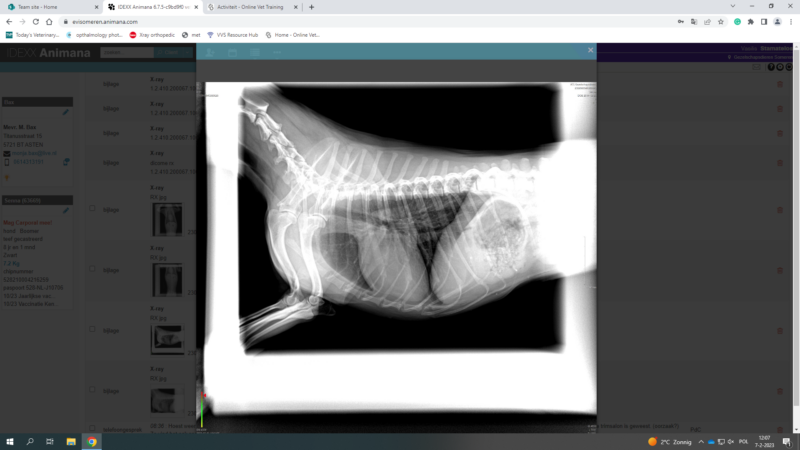

i upload this post in order to discuss one of my cases with you

Its about a yorkshire terrier, 3 years old, female, sterilised, that has coughing problems for 6 months. According with the owner, the problem didnt start 6 months ago, but earlier. But the last 6 months is really getting worse. Before it was once per week…